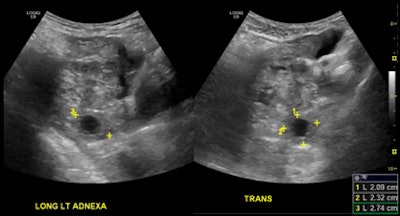

At Santa Barbara Cottage Hospital, ER physicians perform and interpret bedside obstetric ultrasounds -- frequently just transabdominal studies -- using compact ultrasound systems, while radiology ultrasound exams, which include both transabdominal and transvaginal studies, are supervised and interpreted by radiologists. The radiology ultrasound exams are performed in the radiology department by sonographers certified by the American Registry for Diagnostic Medical Sonography (ARDMS), who are available 24/7 to scan patients, according to the group.

For the remaining 75 cases, three radiologists certified by the American Board of Radiology independently reviewed just the final reports of both the emergency medicine physicians and the radiologists. The reviewers determined if there was significant concordance or discordance in a yes/no fashion, and a majority vote was used to make the final ruling; discrepancies were considered significant if they included disagreement over the presence of intrauterine pregnancy, gestational sac, fetal demise, and ectopic pregnancy in the presence of a positive pregnancy exam.